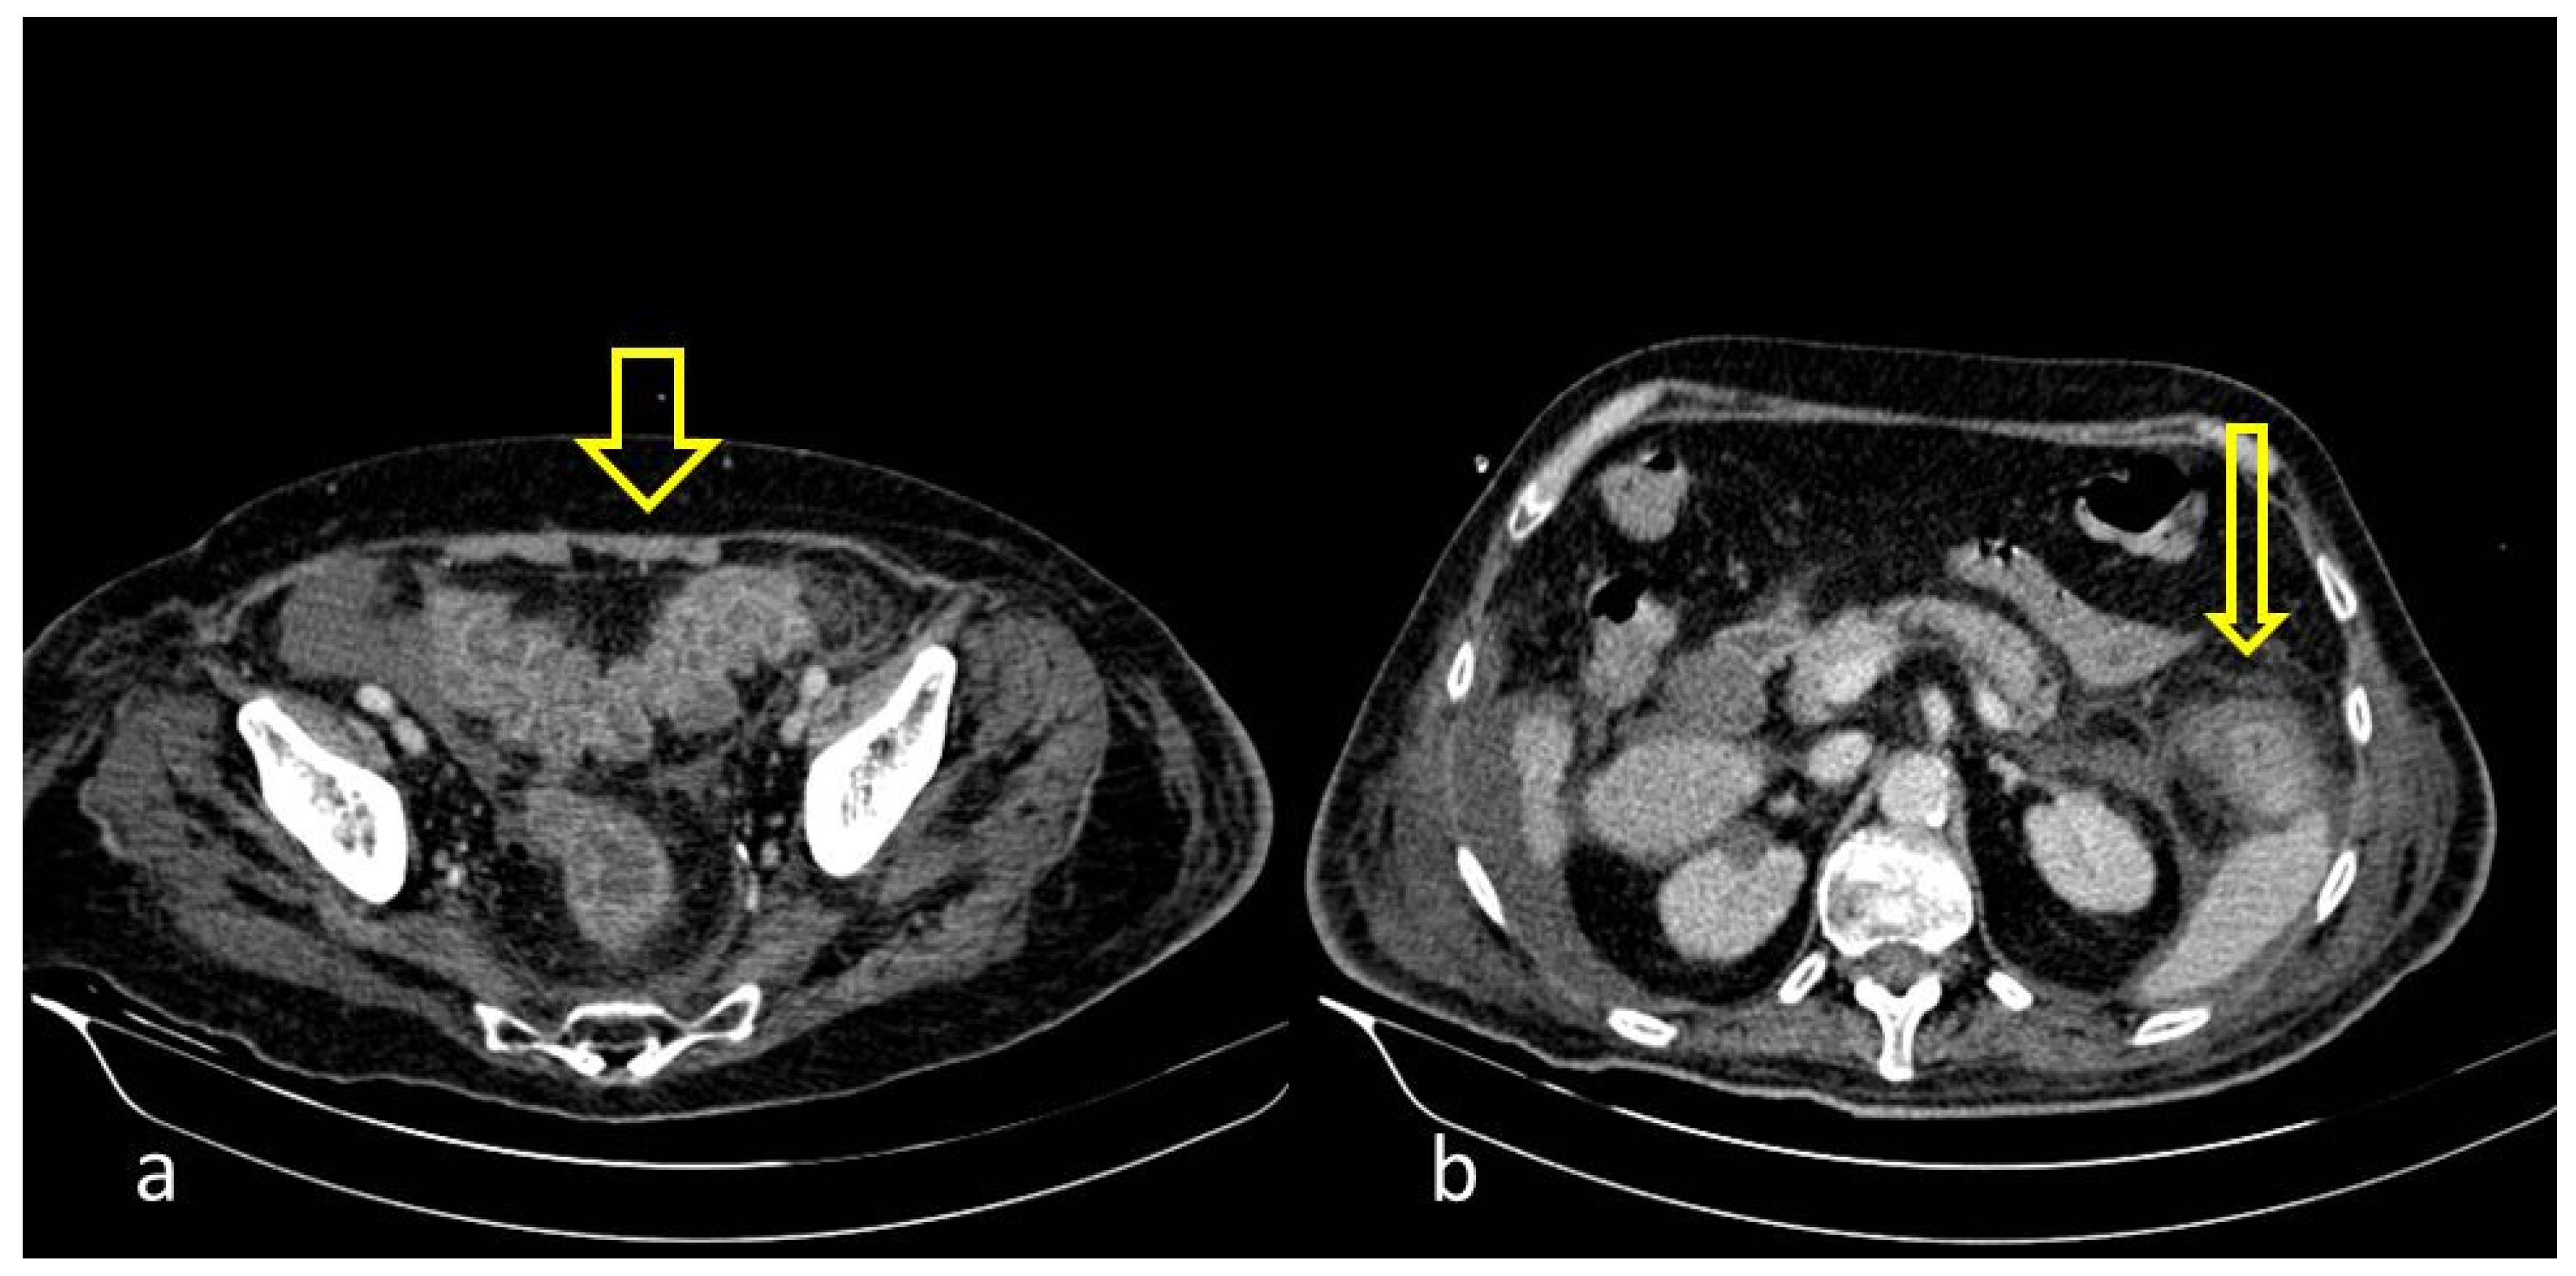

Figure 2. COVID-19 (+) 68-year-old patient with a long hospital stay was subjected to an abdominal CECT for acute abdominal pain, which showed colonic wall thickening ((a), thick arrow) and adjacent fat stranding ((b), thin arrow).

A large bowel infection usually appears with diffuse circumferential and enhancing wall thickening (hyperenhancement) that can involve one or more segments of the colon (Figure 1 and Figure 2). Pericolic fluid or perintestinal fat stranding is common while pericolic lymphadenopathy is not (Figure 3 and Figure 4). If we suspect COVID-19-related colitis, clinical correlation is needed, and the detection of the virus in stools can establish the diagnosis.